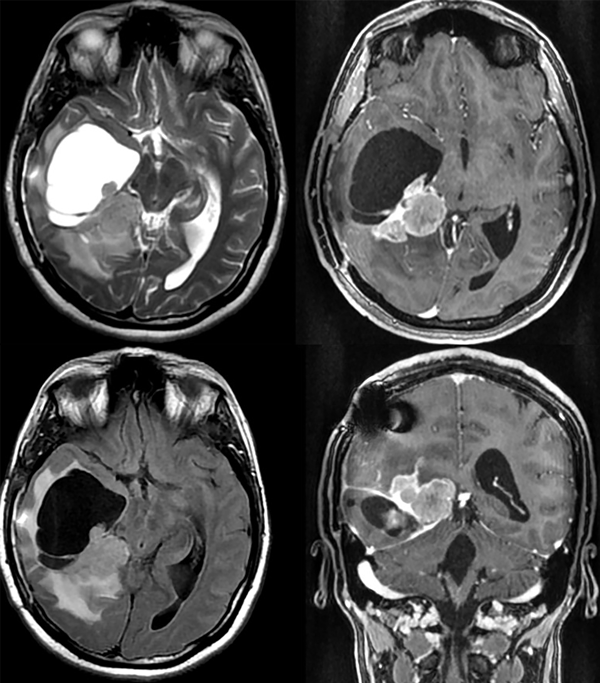

En sucesivos controles la paciente presenta un deterioro de su estatus previo, con signos clínicos de hipertensión endocraneana (cefalea y episodios aislados de náuseas y vómitos), por lo que se indica una nueva RM. La resonancia es realizada a los cinco meses de la intervención quirúrgica (Figura 4).

Figura 4. Se observa una importante recidiva de la masa tumoral con efecto de masa y secuestro ventricular temporal derecho.